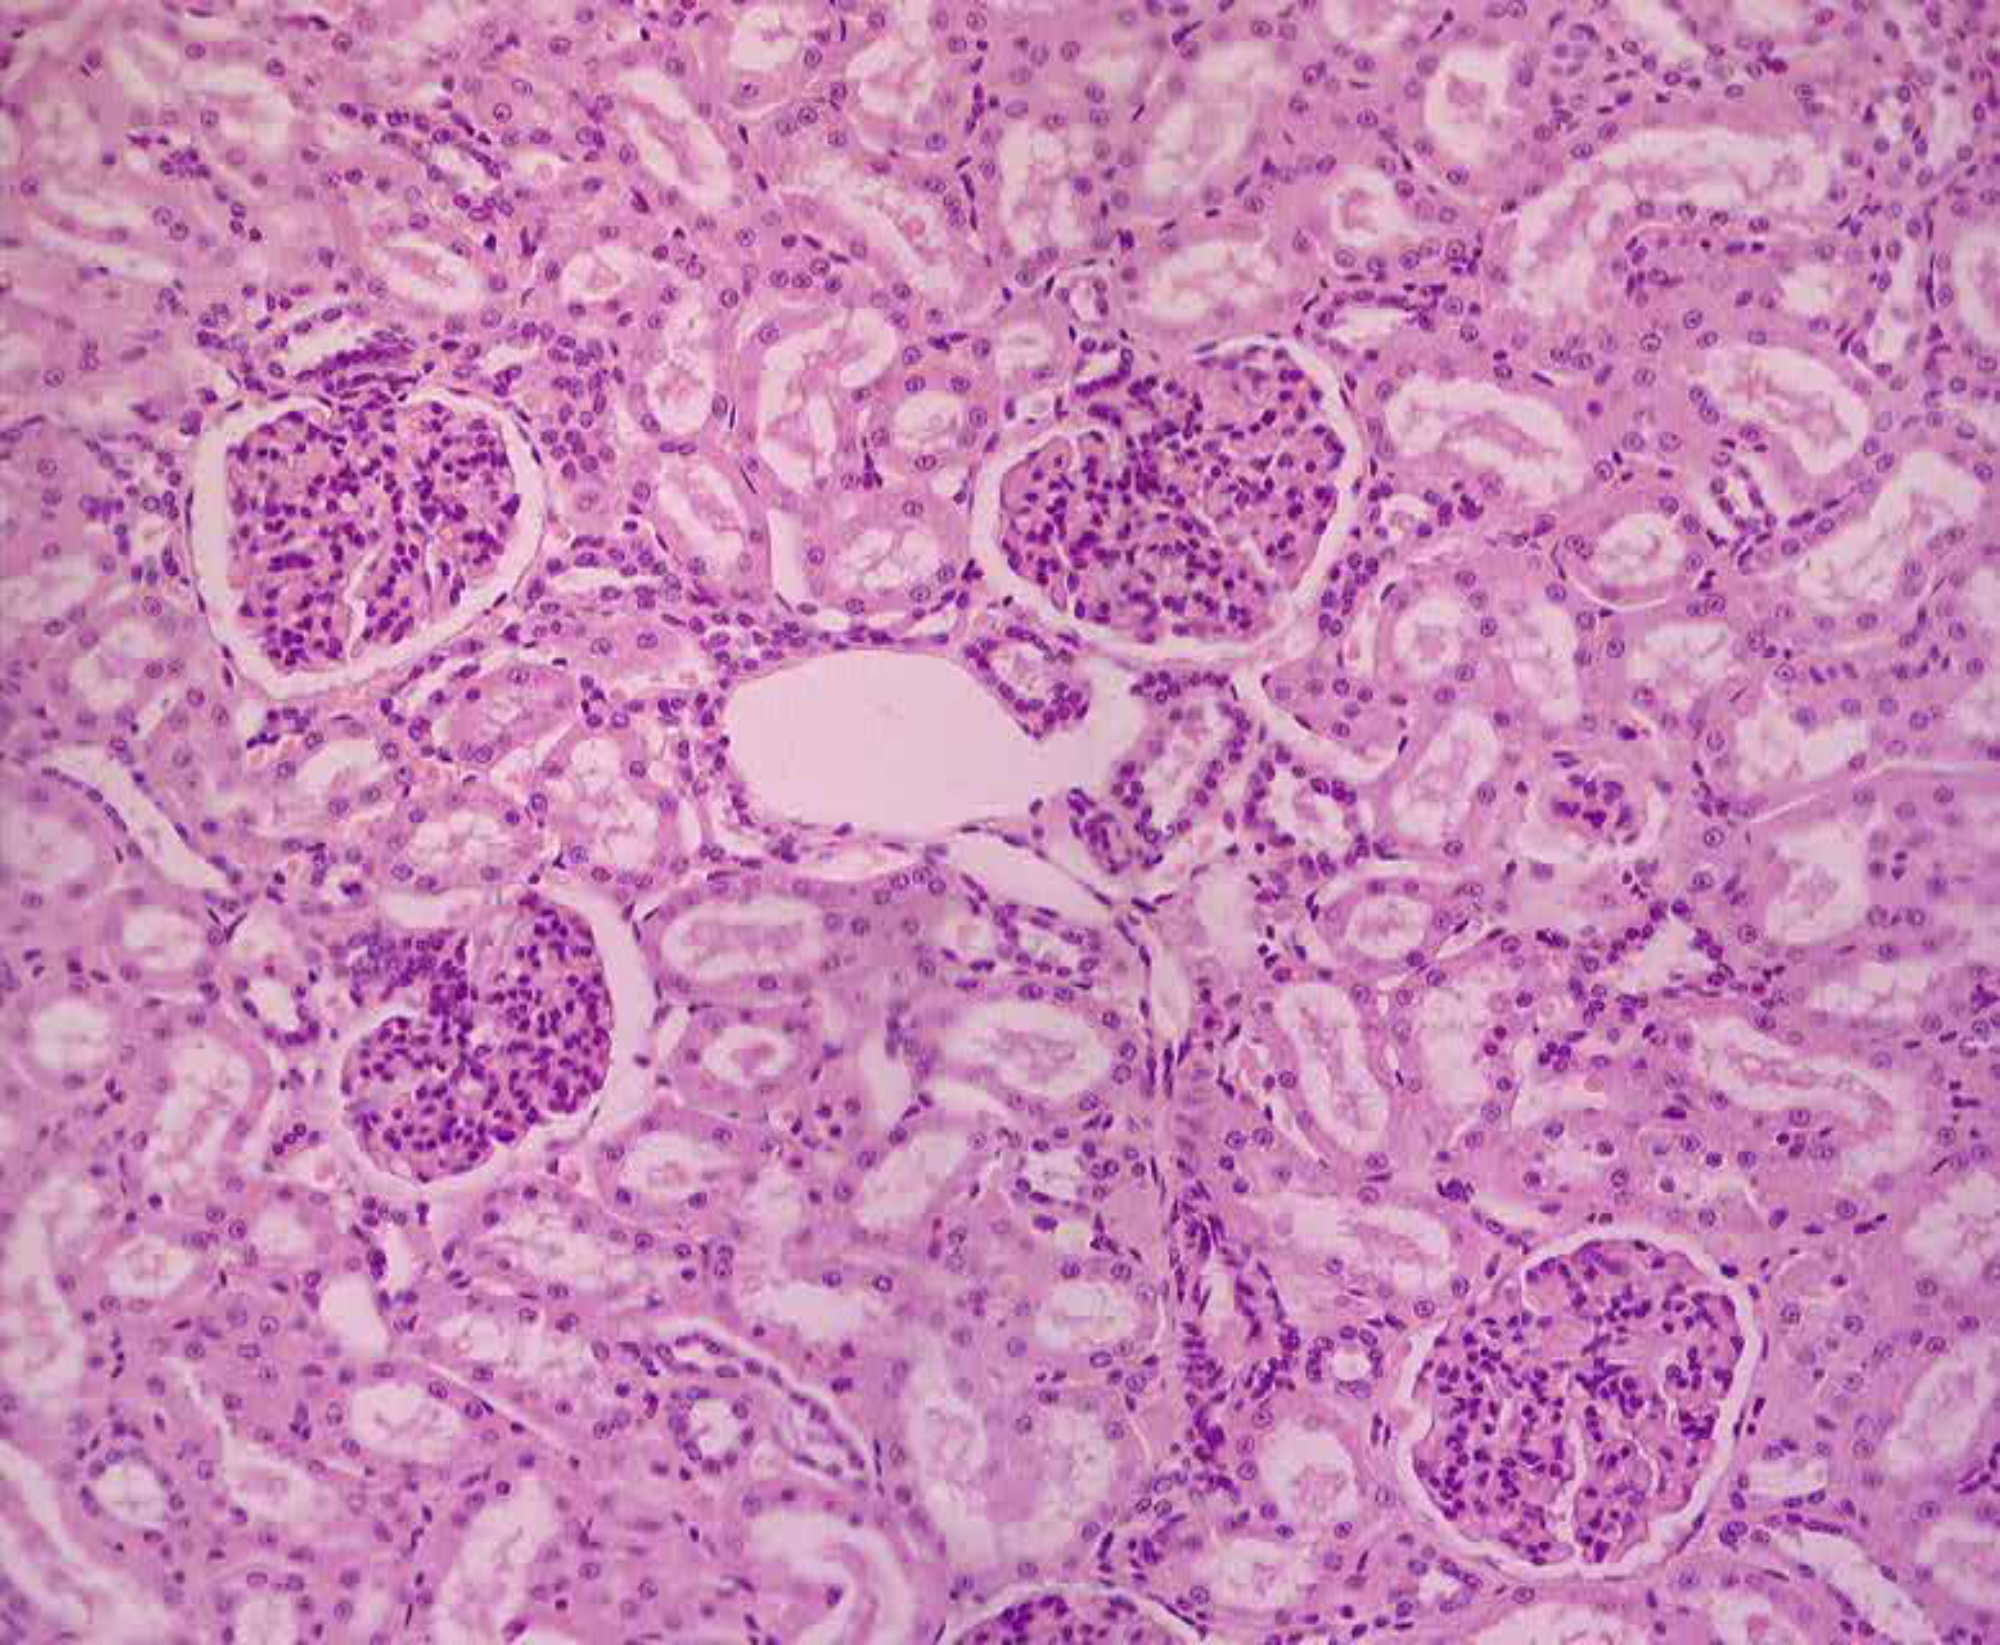

Kidney

1Renal tubules

2Glomeruli

3Renal corpuscles

+1 more points